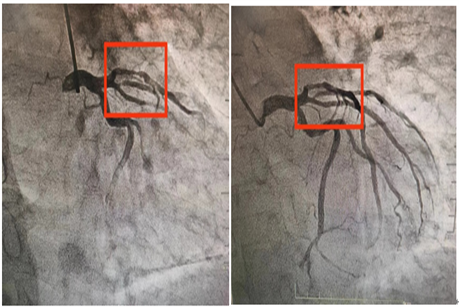

患者为一名老年男性,既往有高血压、高脂血症和长期吸烟史。此次因“冠心病、不稳定性心绞痛”收入我院心内科。冠脉CTA提示:前降支近中段钙化并轻中度狭窄。冠脉造影提示:前降支近中段轻度钙化并临界病变。为精准评估治疗患者的血管病变,我院心内科团队利用IVUS技术精准评估管腔的状况。结果显示,近段测量管腔面积非常狭小,并伴有环形钙化以及明显钙化结节,手术难度极高。

在此背景下,心内科团队在赵慧强主任的带领下,果断采用冠状动脉钙化病变旋磨术(RA)结合切割球囊预处理技术,成功清除了钙化结节及环形钙化病变,为支架植入创造了有利条件。手术过程顺利,患者预后良好。

此病例依托IVUS评估钙化病变情况,采用冠状动脉钙化病变旋磨术及切割球囊给予预处理钙化结节及环形钙化病变,最终成功植入支架,这一“硬核组合”不仅彰显了我院在复杂冠脉病变处理方面的卓越能力,也进一步巩固了医院在心血管介入领域的领先地位。